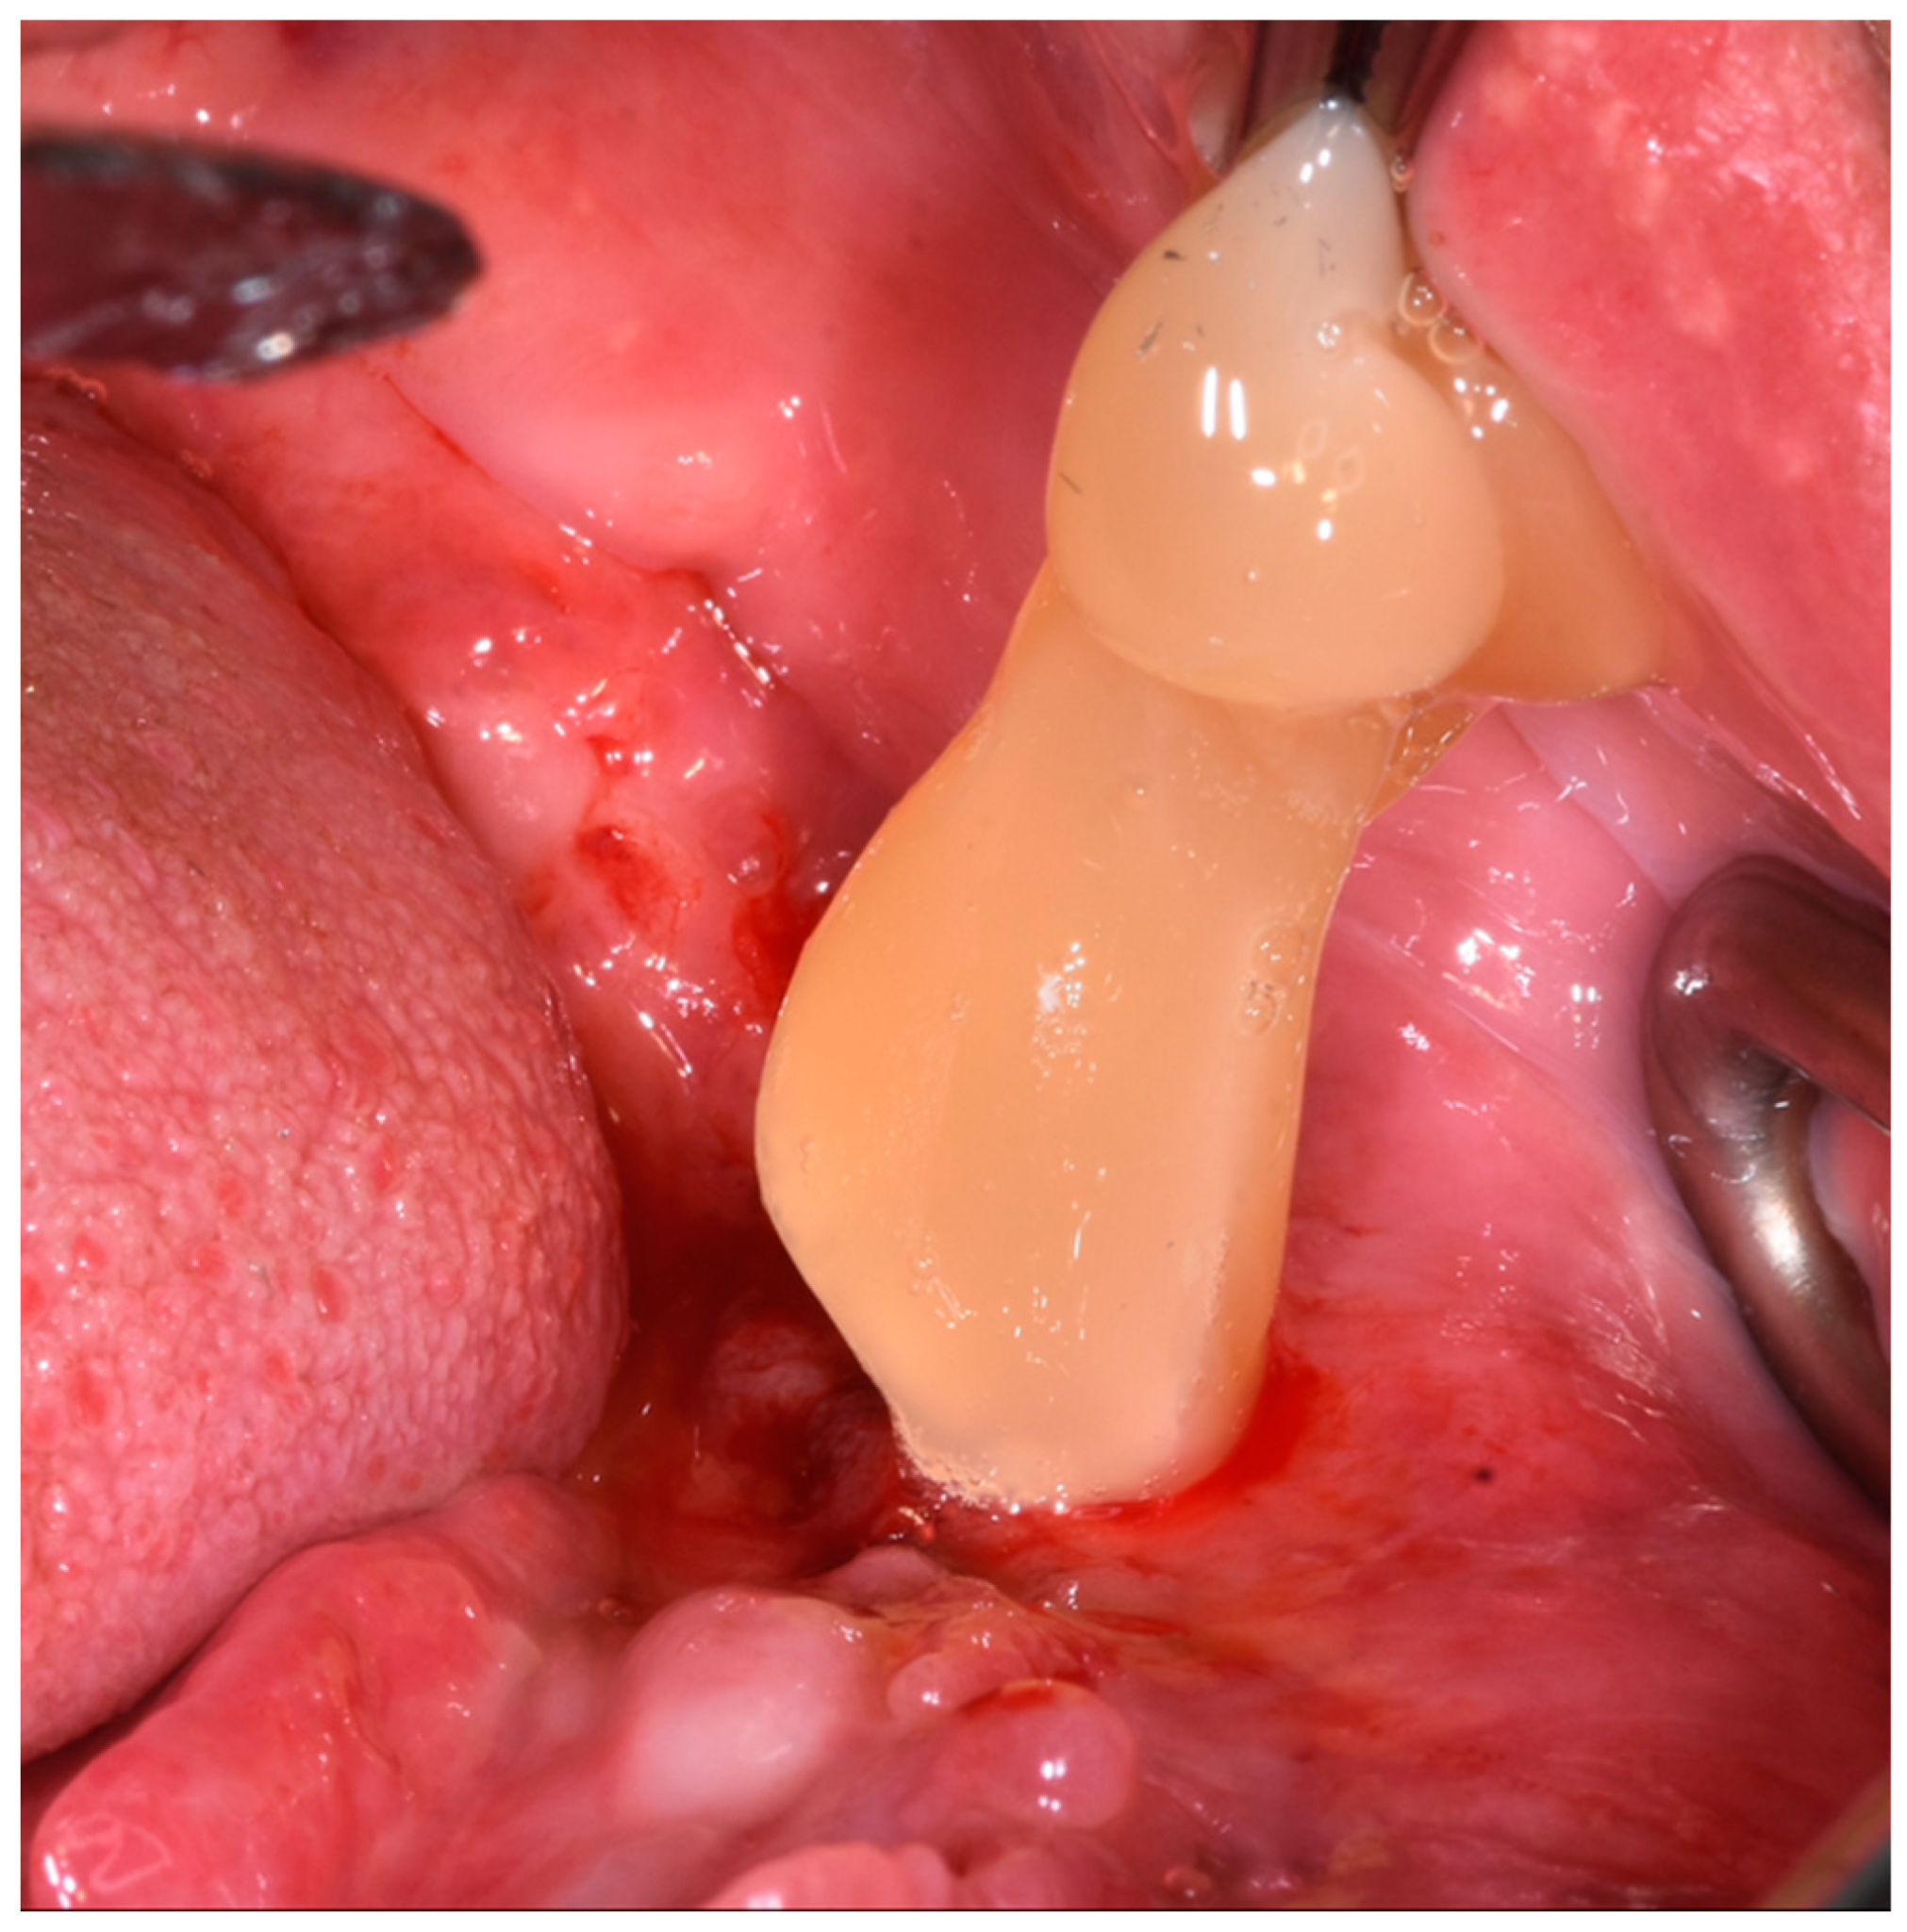

- Left lower neoformation in the area of the first left lower molar

- Excision of the neoformation near the first lower left molar and subsequent histological analysis

2.1.1. Surgery Appointment (September 2021)

2.1.2. Histological Analysis